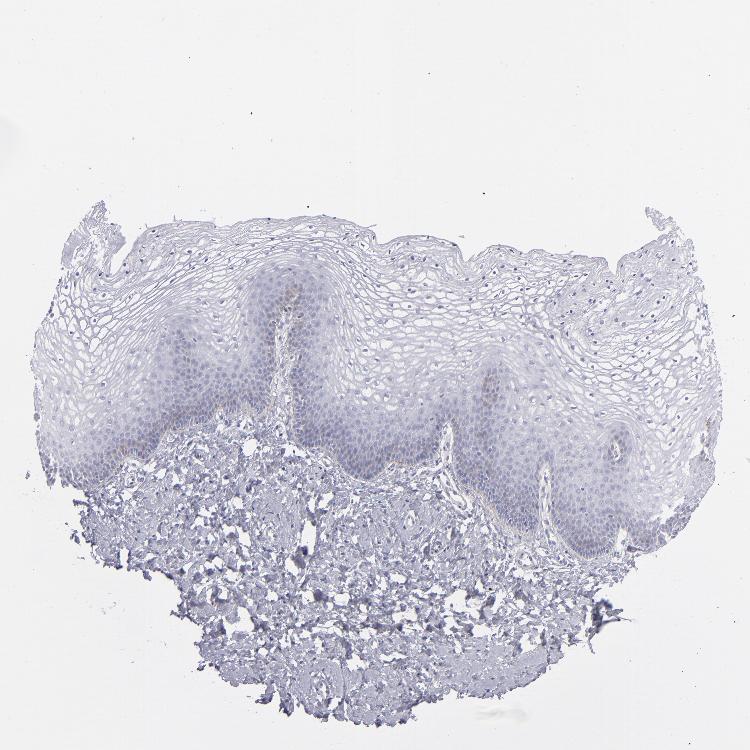

TISSUE PRIMARY DATA VAGINA Show tissue menu

VAGINA - Antibody stainingi

Antibody staining in the annotated cell types in the current human tissue is reported as not detected, low, medium, or high, based on conventional immunohistochemistry profiling in selected tissues. This score is based on the combination of the staining intensity and fraction of stained cells.

Each image is clickable and will lead to virtual microscopy that enables deeper exploration of all samples and also displays staining intensity scores, fraction scores and subcellular localization as well as patient and tissue information for each sample.

Antibody HPA036348Antibody HPA036349Antibody CAB002422Antibody CAB005258

Squamous epithelial cells MediumMediumNot detectedLow